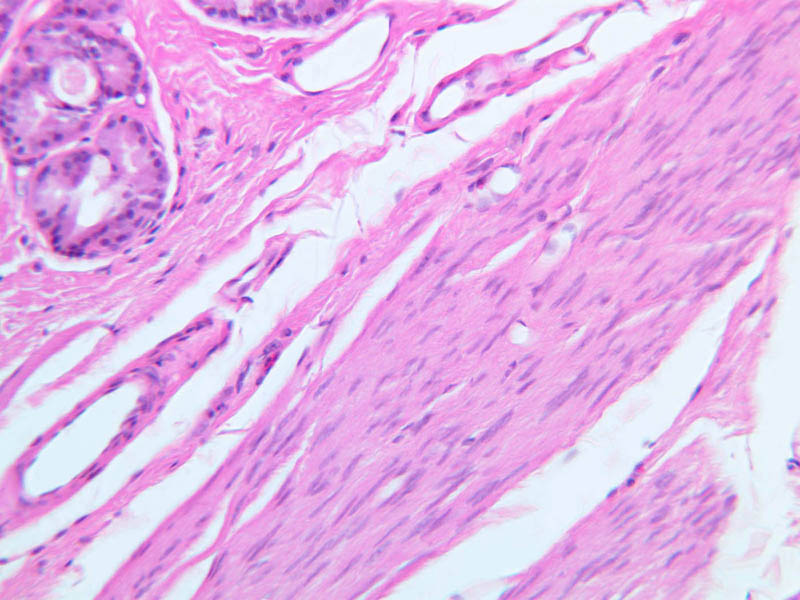

The larynx (A-73 [2.5x, 10x, 20x, 40x] [2.5x, 10x, 20x, 40x]) is kept open by a series of cartilaginous rings. Characterize the cartilage in the walls as to type and extent. The particular importance of the larynx is clearly demonstrated in its use for the generation of sounds. The lining epithelia, the fibrous elements of the vocal cords and muscles attached to the cords are adapted for this purpose. The respiratory epithelium of upper and lower larynx is replaced over the vocal cords by a thin stratified squamous epithelium. The body of the cords consists of skeletal muscle and elastic connective tissue. Numerous examples of both serous and mucous glands can be seen everywhere beneath the laryngeal epithelium except in the vocal cords themselves ([2.5x, 10x, 20x, 40x-labeled]). Occasional lymphoid nodules may also occur ([2.5x, 10x, 20x, 40x]).